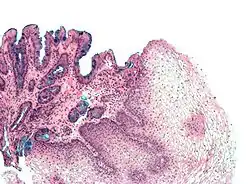

ظهارة حرشفية مطبقة

هي طبقتين أو أكثر من الخلايا الحرشفية تمتاز بشكل مسطح، تقع هذه الخلايا فوق الغشاء القاعدي لكن طبقة واحدة فقط تتصل بالغشاء القاعدي مباشرةً، الطبقات الأخرى تتماسك بعضها ببعض كي تحفظ شكلها الكامل، بالرغم أن طبقات الظهارة الحرشفية المطبقة تحتوي على خلايا حرشفية التي تمتاز بشكلها المسطح غالباً إلا أن بعض هذه الخلايا ليست مسطحة الشكل.

الظهارة الحرشفية المطبقة مناسبة جداً للأماكن التي يجرح فيها الإنسان، يحدث هذا بسبب القدرة الفائقة للظهارة على نزع الخلايا التالفة وتعويضها بسرعة بخلايا جديدة قبل أن يتعرض الغشاء القاعدي لتلف.

سرطان الخلية الحرشفية الظهارية

و يتضمن سرطانة حرشفية الخلايا وسرطان الخلايا القاعدية وأورام أخرى.